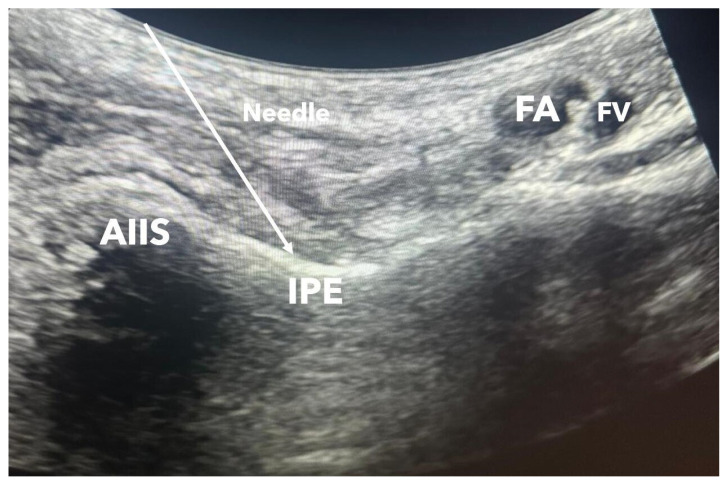

Background/aim: The pericapsular nerve group (PENG) block is an effective method for pain management in patients with hip fractures. In our study, we compared three different local anesthetic volumes of the PENG block in patients who underwent surgery for hip fracture.

Materials and methods: Patients who underwent surgery with spinal anesthesia for intertrochanteric femur fractures (60 patients) were divided into three groups based on the volume of local anesthetic administered: Group 1 (20 mL), Group 2 (30 mL), and Group 3 (40 mL). Postoperative patient-controlled analgesia was initiated. Postoperative tramadol consumption, rest and movement pain scores, and the duration of motor block were monitored.